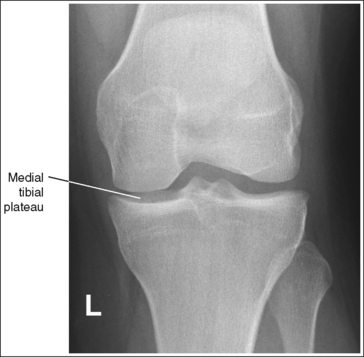

• Analysis of joint space narrowing. On an AP knee projection with adequate positioning, joint space narrowing is evaluated by measuring the medial and lateral aspects of the knee joint, which are also referred to as compartments. The measurement of each of these compartments is obtained by determining the distance between the most distal femoral condylar surface and the posterior condylar margin of the tibia on each side. Comparison of these measurements with each other, with measurements from previous images, or with measurements of the other knee determines joint space narrowing or a valgus or varus deformity. In a valgus deformity the lateral compartment is narrower than the medial compartment; in a varus deformity the medial compartment is narrower (see Images 56 and 57). Precise measurements of the compartments are necessary to ensure early detection of joint space narrowing and are best obtained when the knee joint space is completely open. If an inaccurate central ray angulation was used for an AP knee projection, the knee joint is narrowed or obscured, the intercondylar eminence and tubercles are foreshortened, and the tibial plateau is demonstrated.

• Effect of poor central ray angulation. When examining an AP knee projection for which an inaccurate central ray angulation was used, you can determine how to adjust the angulation by judging the shape of the fibular head and its proximity to the tibial plateau. If the fibular head is foreshortened and demonstrated more than 0.5 inch (1.25 cm) distal to the tibial plateau, the cephalad angle was too great (see Image 58). If the fibular head is elongated and demonstrated less than 0.5 inch (1.25 cm) distal to the tibial plateau, the caudad angle was too great (see Image 59).

The knee joint space is obscured, the medial tibial plateau is demonstrated, the fibular head is foreshortened and demonstrated more than 0.5 inch (1.25 cm) distal to the tibial plateau. Excessive cephalad angulation is indicated.

Angle the central ray caudally approximately 5 degrees for every 0.25 inch (0.6 cm) of tibial plateau demonstrated. For this image, approximately 0.5 inch (1.25 cm) of the tibial plateau is demonstrated between the anterior and posterior tibial margins. The central ray should be adjusted approximately 10 degrees, because a 5-degree cephalad angle was used. When the image is retaken, a 5-degree caudal angle should be used.